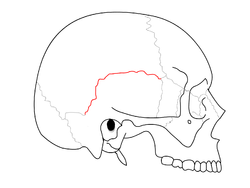

![]() Side view of the skull. Squamosal suture in red. | |

The squamosal suture, or squamous suture, arches backward from the pterion and connects the temporal squama with the lower border of the parietal bone: this suture is continuous behind with the short, nearly horizontal parietomastoid suture, which unites the mastoid process of the temporal with the region of the mastoid angle of the parietal bone.